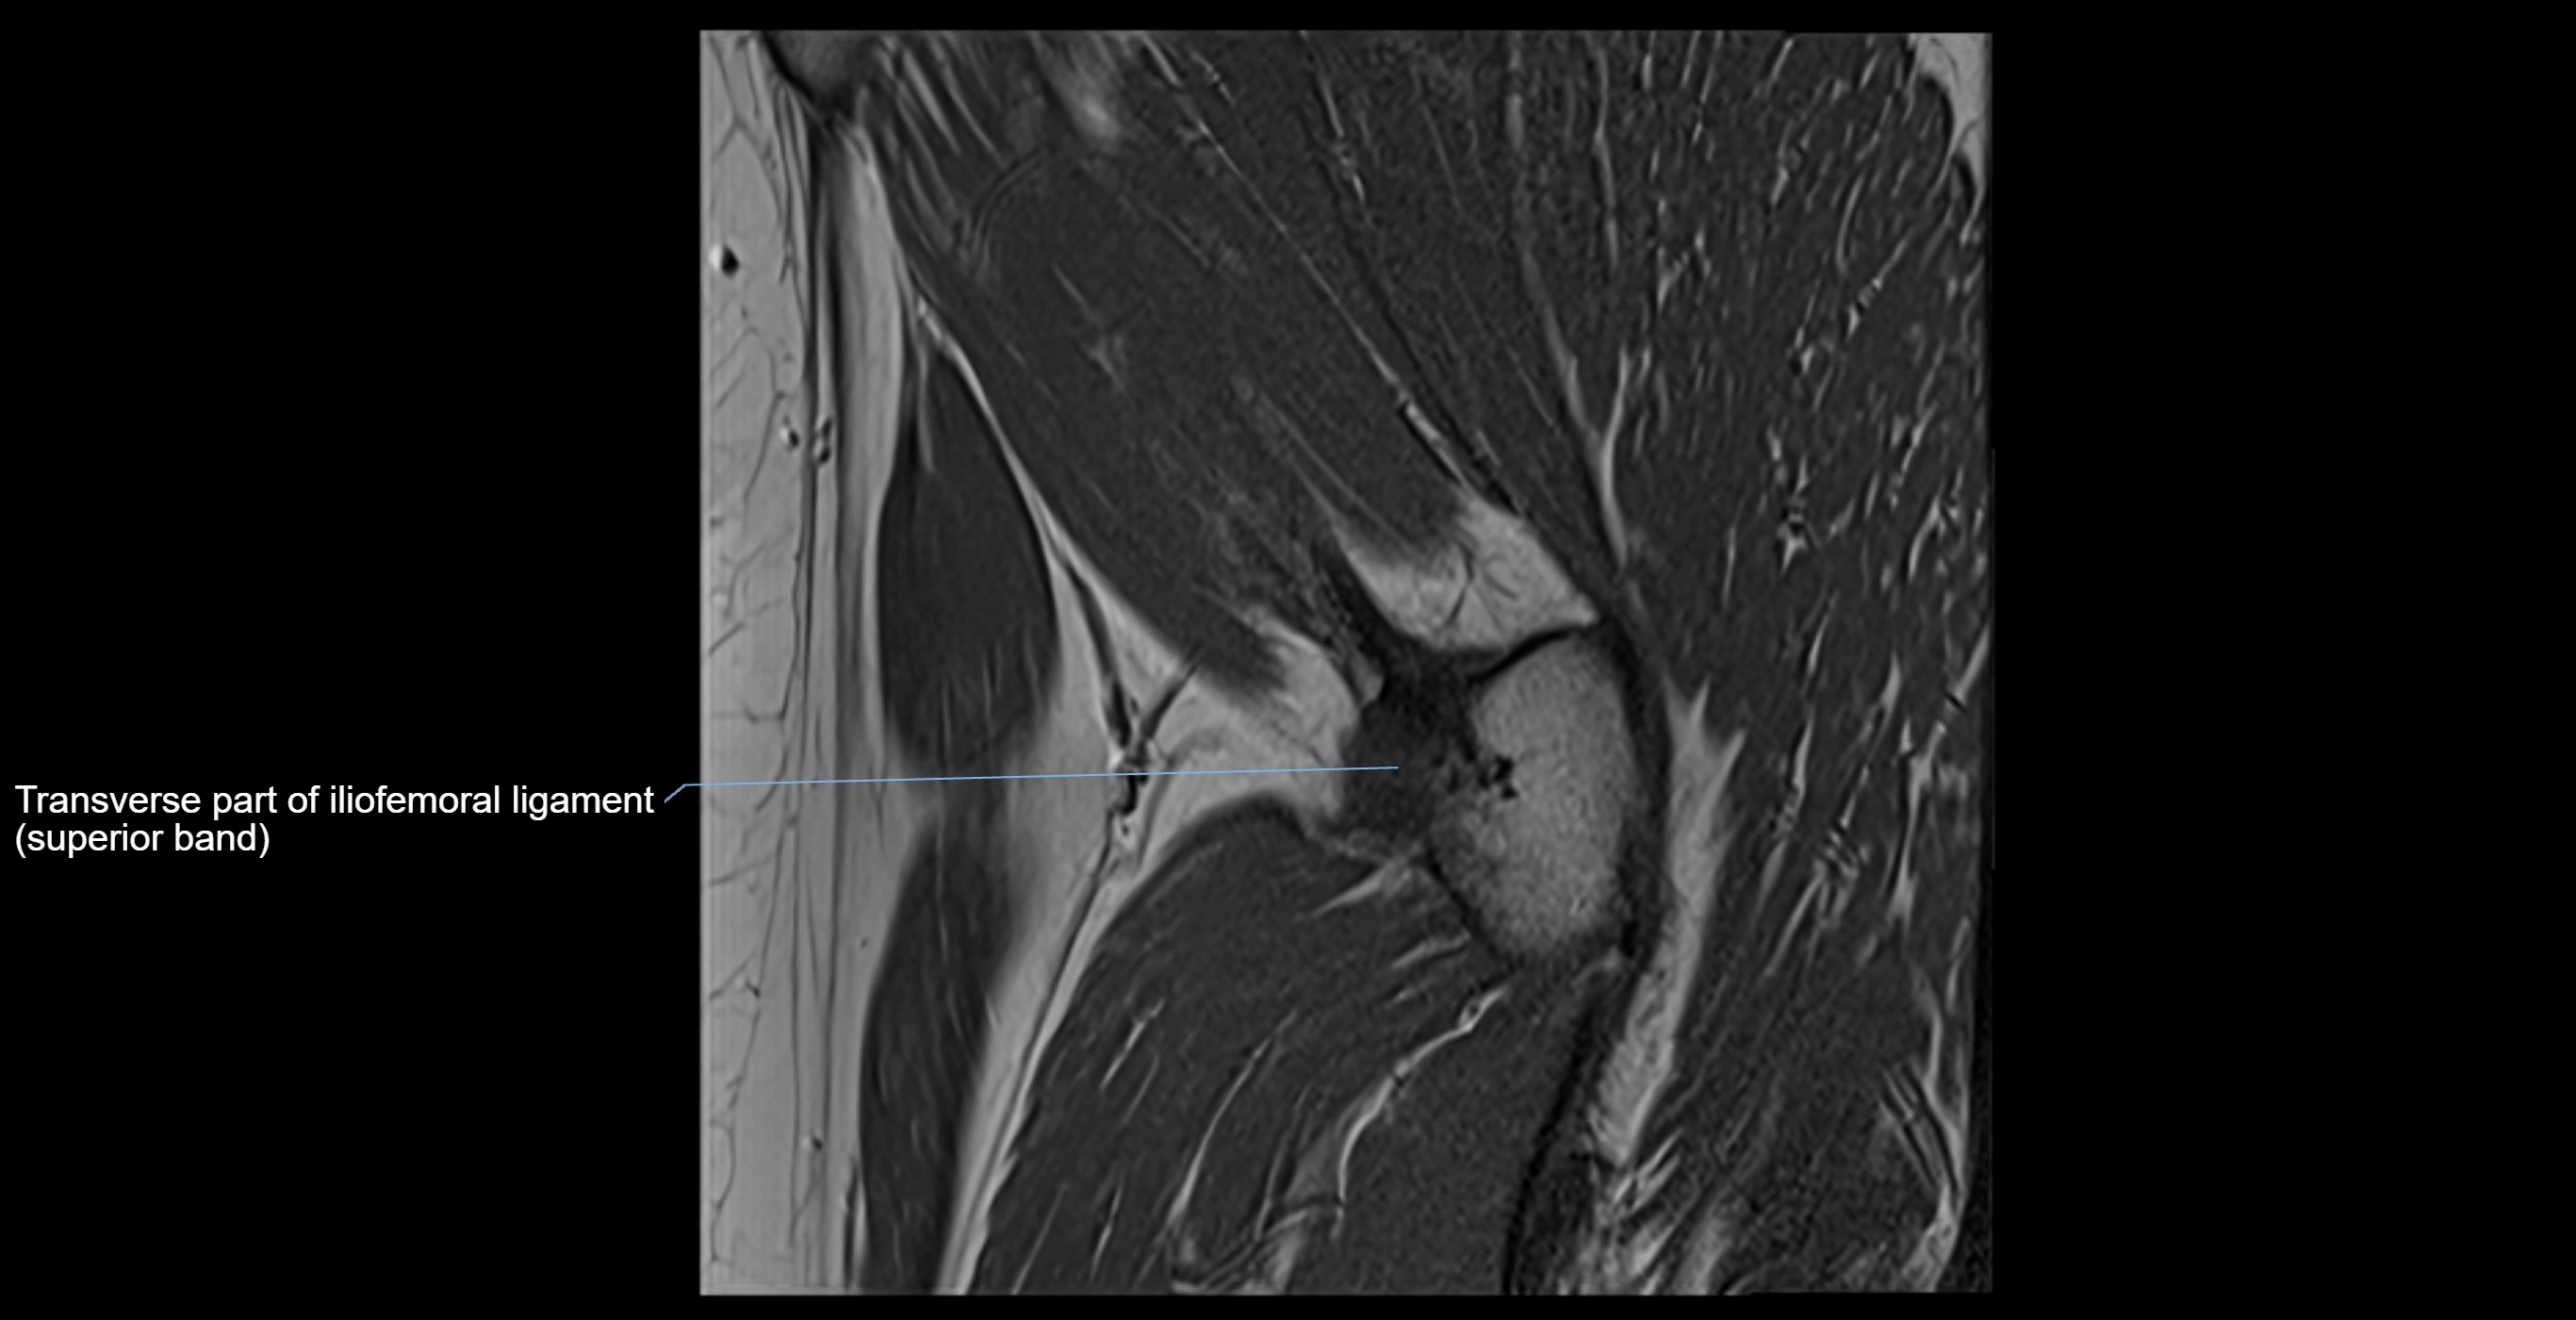

MRI image

image

MRI Appearance

T1-weighted images:

• Labrum: low signal intensity (dark)

• Surrounded by intermediate signal joint fluid (bright on arthrogram)

• Tears: linear or focal areas of intermediate-to-high signal interrupting labral continuity

T2-weighted images:

• Joint fluid: bright, making labral tears visible as fluid extending into or around labrum

• Degeneration: may show areas of increased signal within labrum